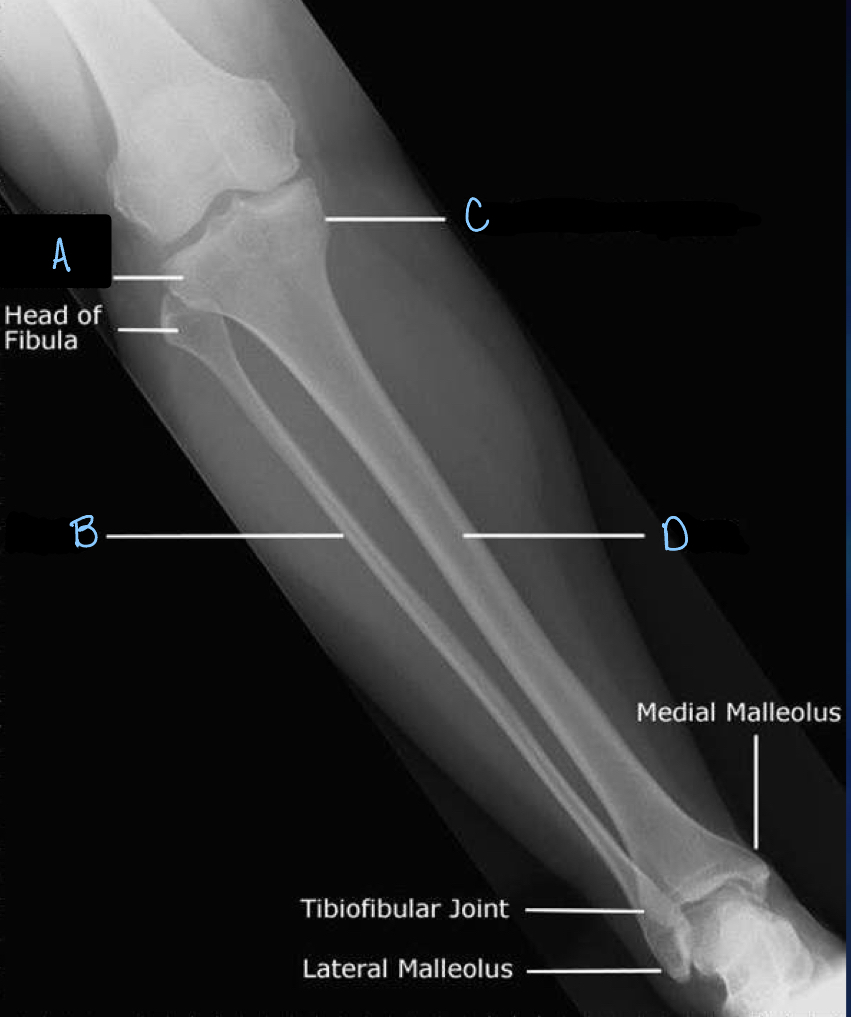

1

What is A?

lateral tibial condyle

2

What is B?

fibula

3

What is C?

medial tibial condyle

4

What is D?

tibia